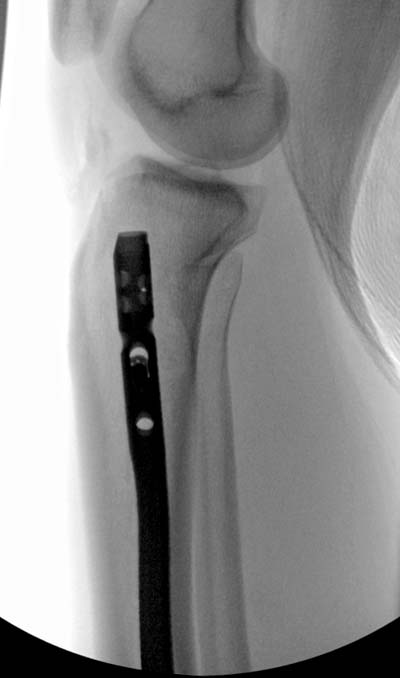

Здесь несколько снимков изолированного перелома большеберцовой с

интактной малоберцовой.  Weber clamp, блокирующие спицы и риминг в

центре канала отрепонировал перелом....